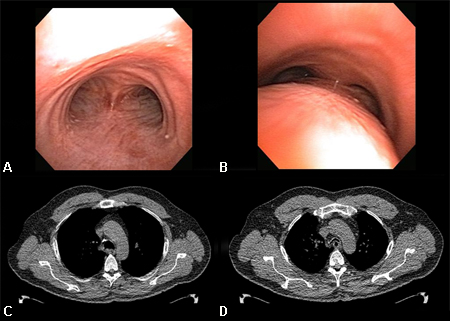

Динамический коллапс дыхательных путей: A. бронхоскопическая проекция на вдохе; B. бронхоскопическая проекция на выдохе, которая показывает динамический коллапс дыхательных путей; C. КТ грудной клетки, которая показывает нормальные дыхательные пути на вдохе; D. КТ грудной клетки, которая показывает значительный коллапс дыхательных путей на выдохе

Из коллекций Хосе Фернандо Сантакруза, дипломированного врача, члена Американской коллегии специалистов в области торакальной медицины, DAABIP, и Эрика Фолка, дипломированного врача, магистра наук; используется с разрешения